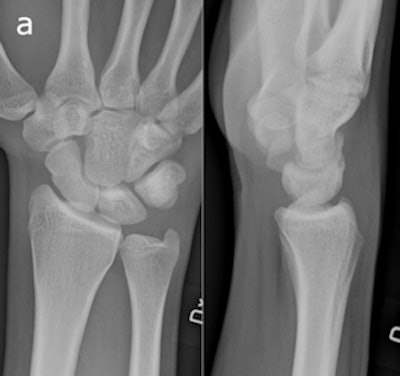

A 20-year-old man who had initial negative wrist and scaphoid radiographs. The follow-up radiograph (a) was normal. No fractures were observed in enlargements of the wrist radiographs and two scaphoid views (b). All images reprinted with permission of Springer Publishing.

Injuries were stabilized in a plaster cast for two weeks. One patient declined to participate in the trial. Follow-up imaging for the remaining 35 patients was performed at a separate site at some distance away from the ER, where CR and tomosynthesis could be performed in sequence. In actual practice, the optimal use of musculoskeletal tomosynthesis will be found by placing the equipment in the ER, Geijer noted in an e-mail to AuntMinnie.com.